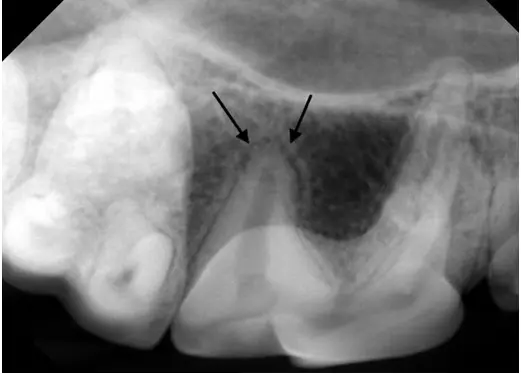

Below is the radiograph from last month, from an endodontically infected tooth. A classic periapical lucency can be seen around the distal root. For comparison, the second X-ray is from the contralateral tooth in the same patient, showing normal anatomy.

For comparison, the dental X-ray taken of the same tooth on the other side shows the normal appearance of the bone and periodontal ligament space around the back root (arrows).